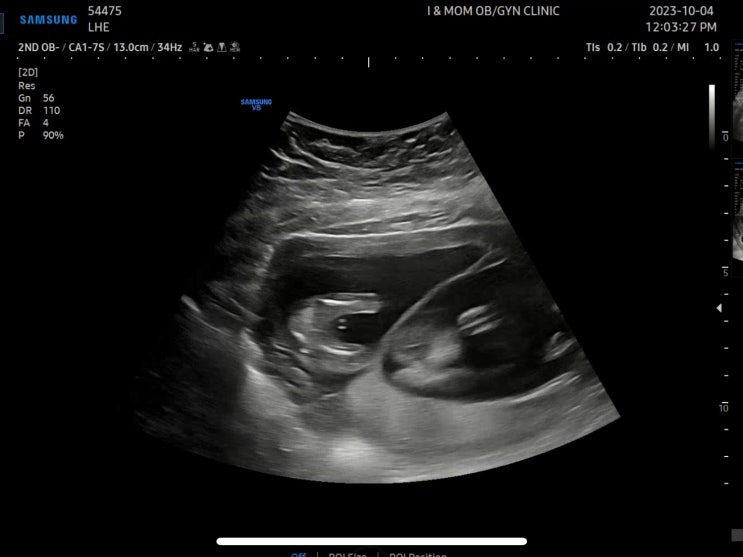

쌍둥이 임신 14-16주차 딸둥이 확정? 2차 기형아검사 감자와눈사람 졸업

10/4(수) 강릉 아이앤맘 피고임 크기 확인 9/25-27 2박3일 입원 후 추석연휴가 지나고 피고임 크기 확인차 ...